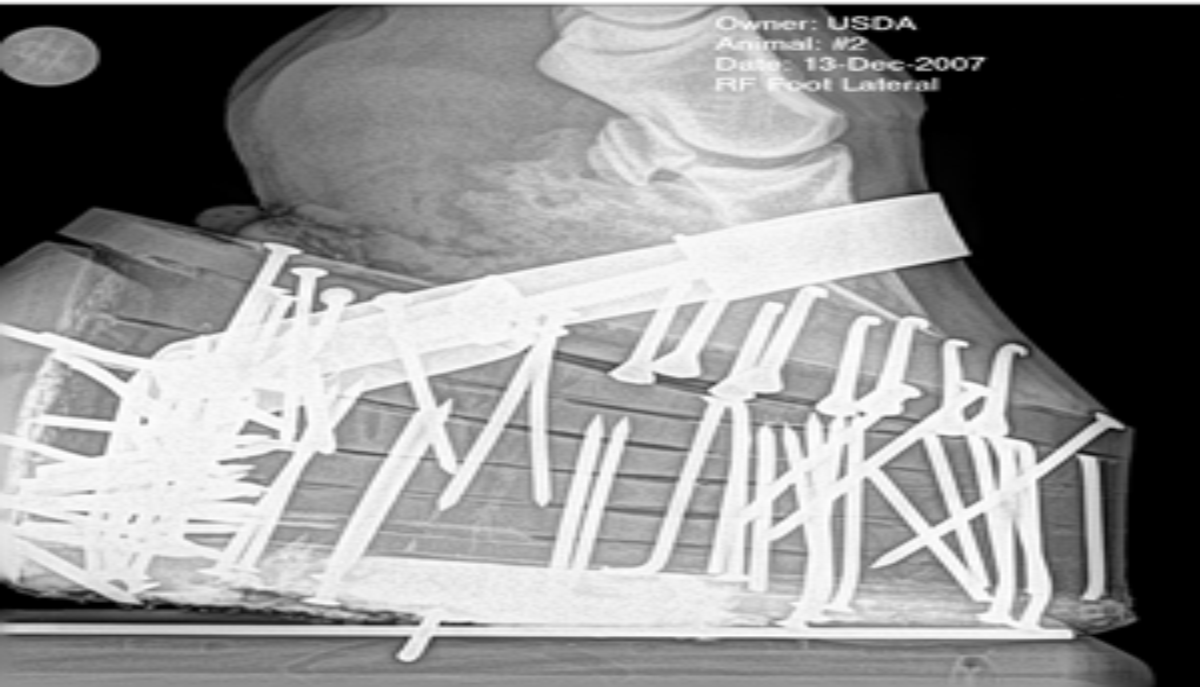

Der Mittelfeldspieler des FC Köln, Jackson Irvine, fällt wegen einer Verletzung am linken Fuß für längere Zeit aus. Der Rückschlag trifft den Verein nur wenige Tage vor dem Nordderby gegen den VfL Wolfsburg. Seine Abwesenheit verschärft ein langwieriges Problem mit demselben Fuß, das ihn bereits in der vergangenen Saison fast sechs Monate außer Gefecht gesetzt hatte.

Irvines Verletzung ist kurz vor dem wichtigen Spiel gegen Wolfsburg erneut aufgeflammt. Der Klub bestätigte, dass er in absehbarer Zeit nicht zur Verfügung stehen wird. Dies folgt auf eine Operation am linken Fuß im April 2025, über deren Details jedoch nichts bekannt wurde.

Der Ausfall des Mittelfeldspielers hinterlässt beim FC Köln eine spürbare Lücke, da einer der Schlüsselspieler auf unbestimmte Zeit fehlt. Die Fußverletzung, die bereits im April 2025 operiert werden musste, wirft ihn weiterhin zurück. Wann Irvine wieder einsatzbereit sein wird, ließ der Klub offen.